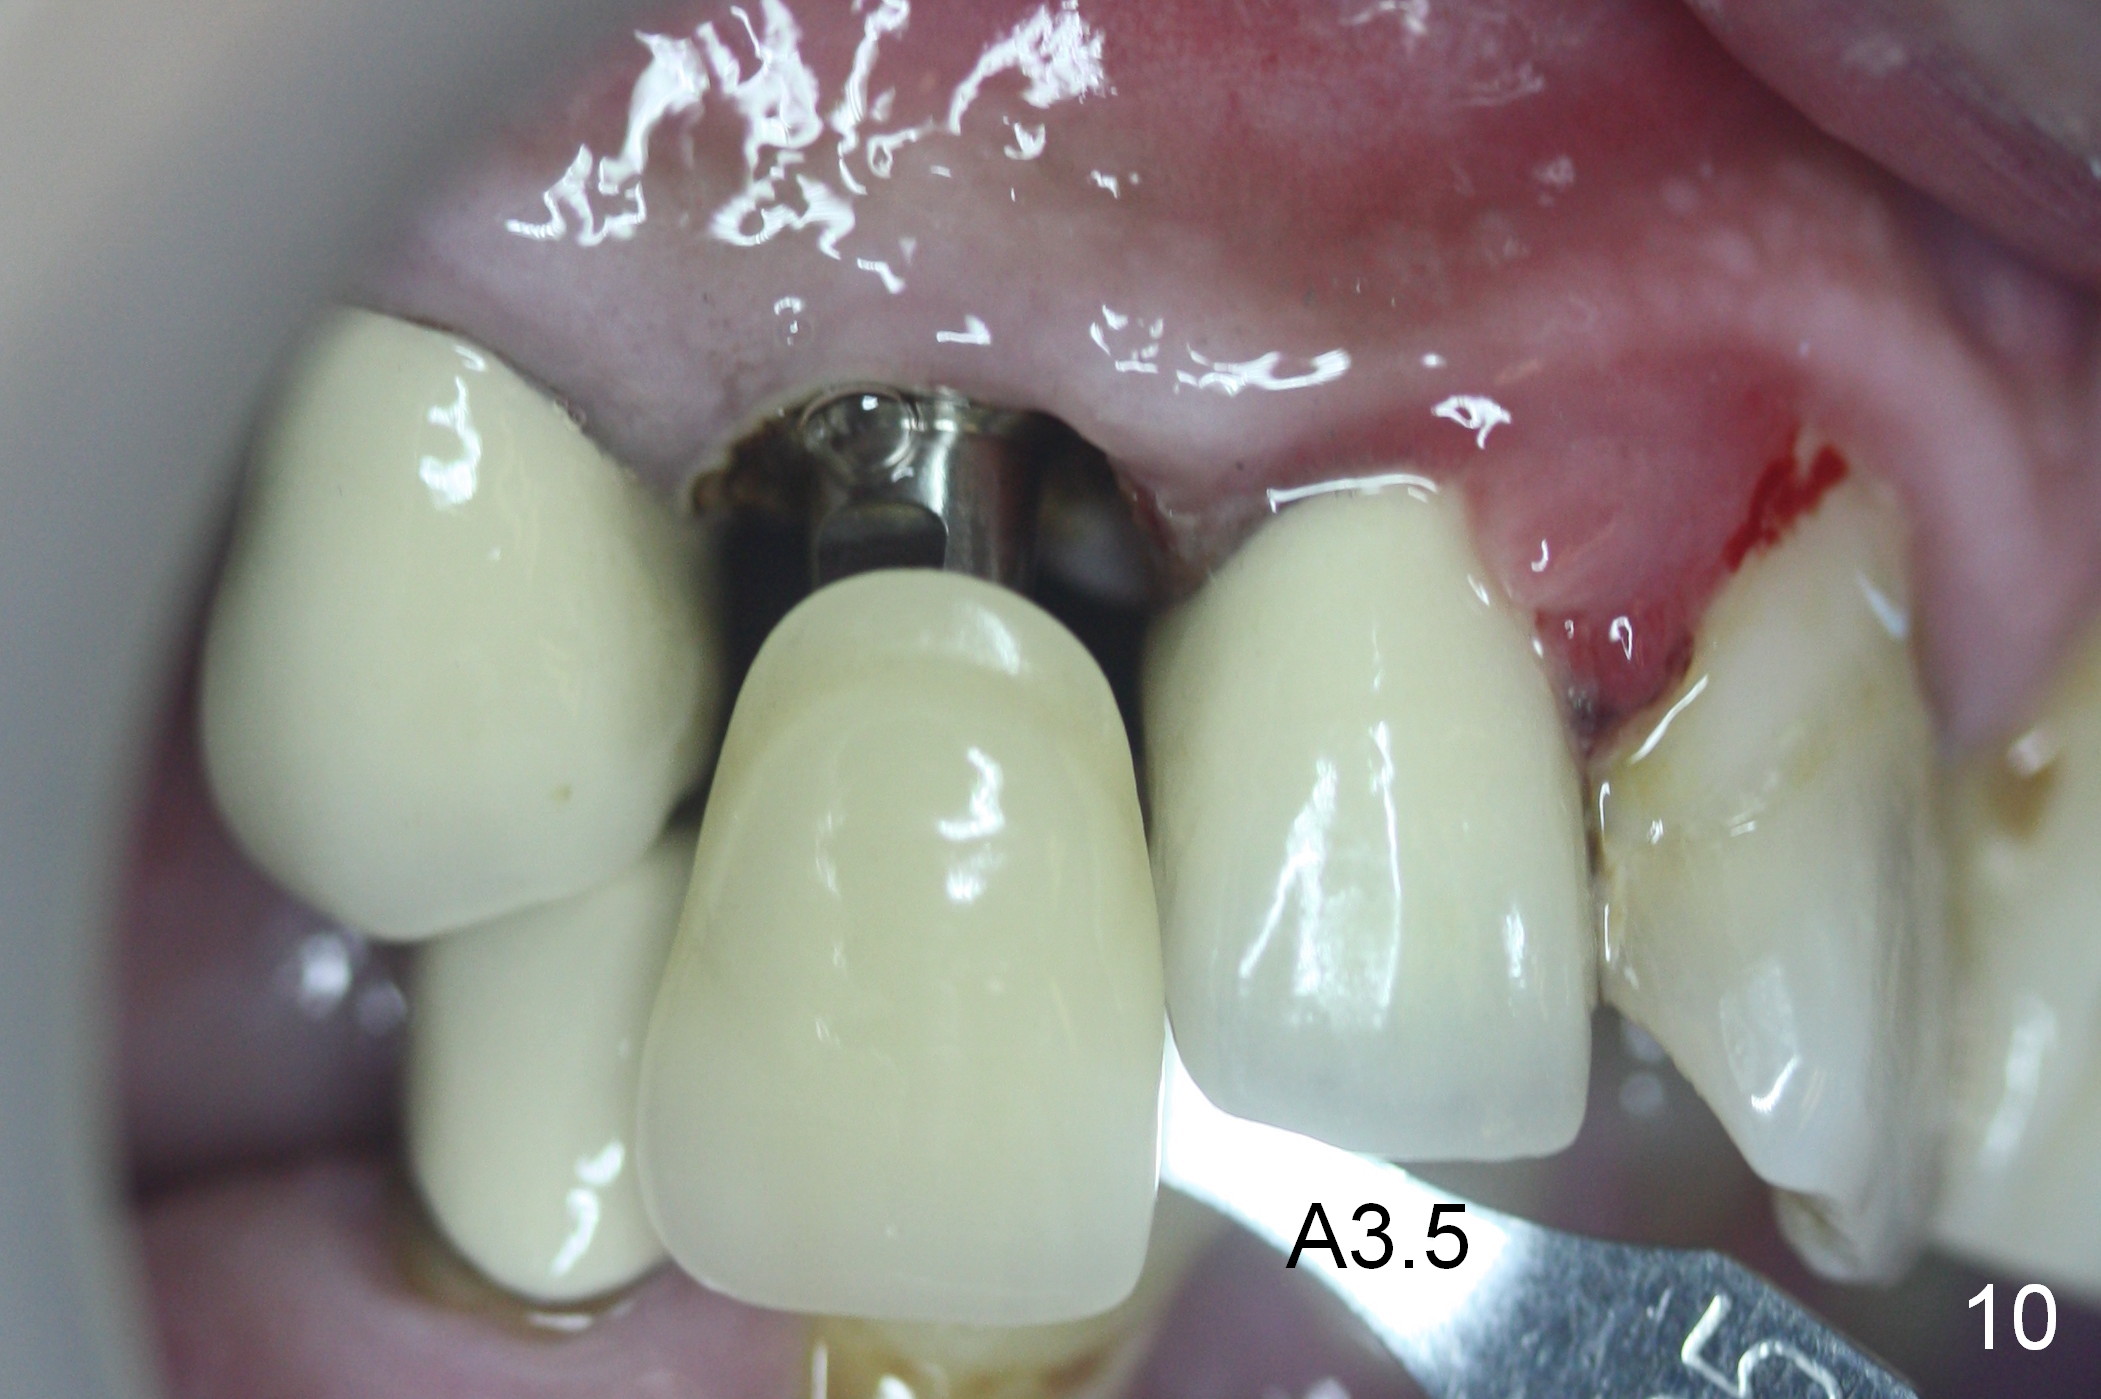

Six days post provisional reline, the mesial papilla erythema has subsided substantially; the abutment is changed to 4.5x5(2) with Diode gingivectomy (Fig.10-12).